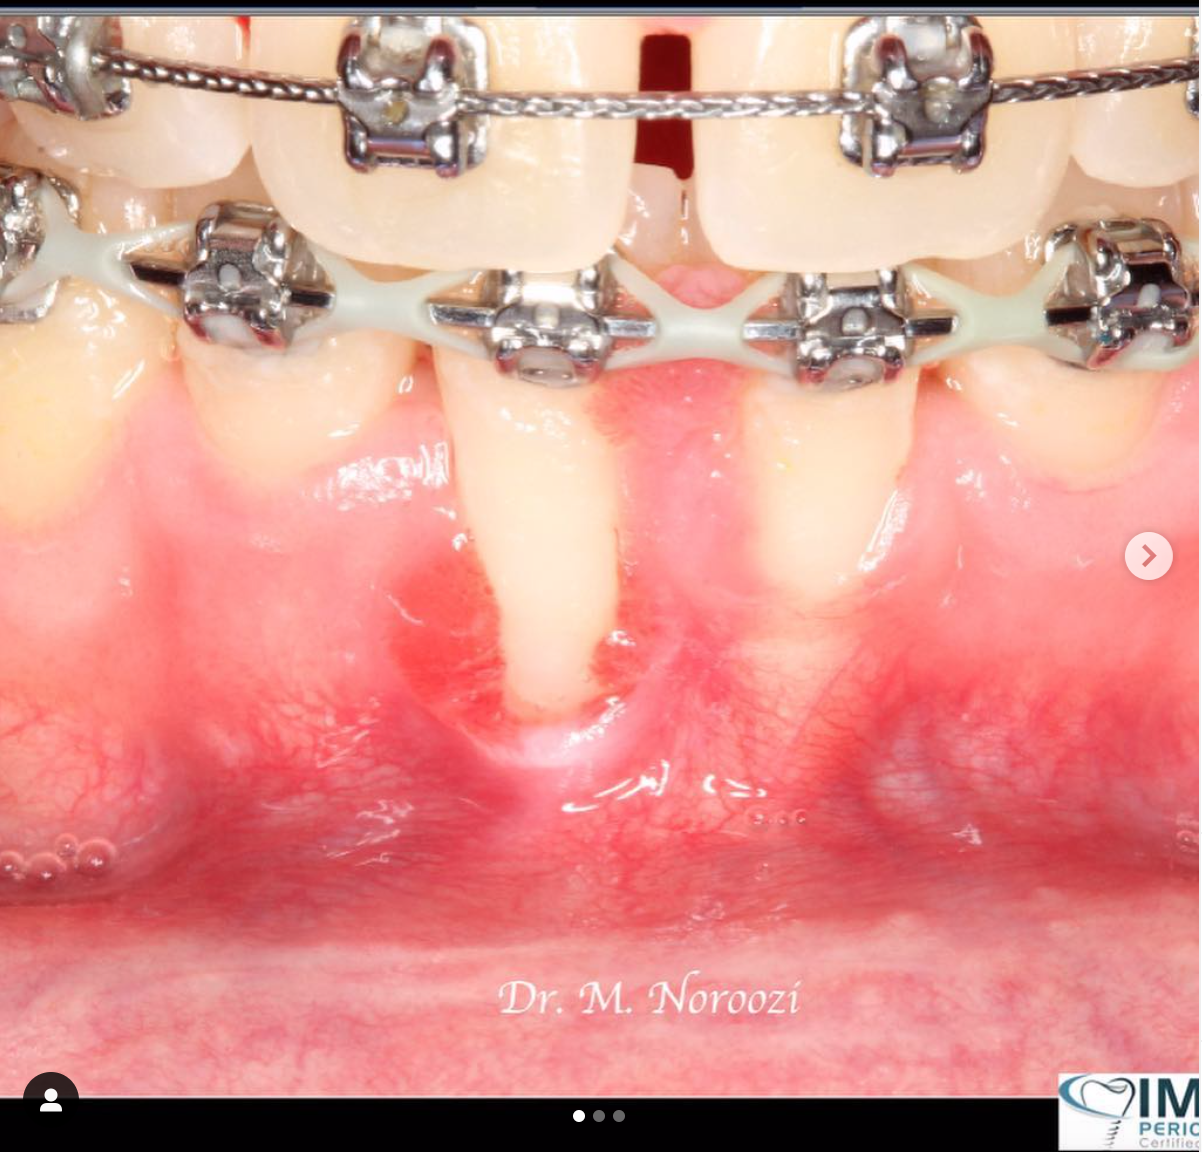

Vertical Bone & Gum Augmentation & Guided Implant Placement